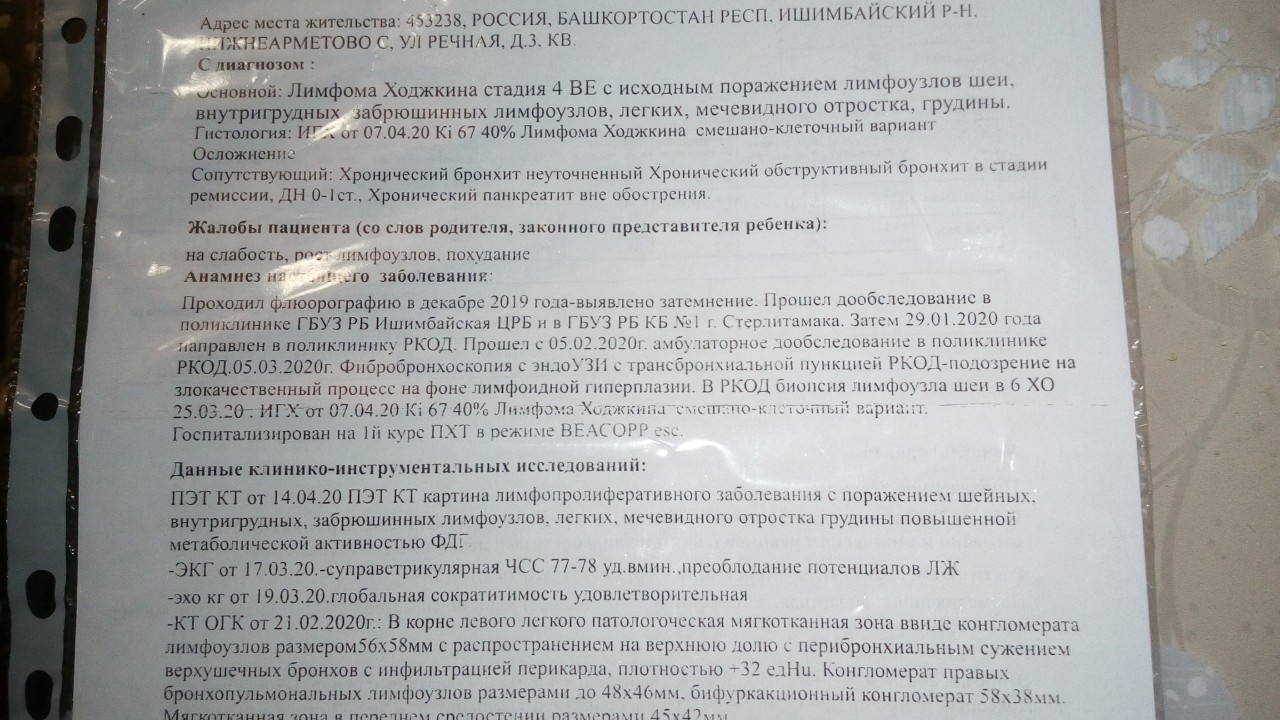

Диагностика лимфомы Ходжкина с помощью ПЭТ и КТ

Раздел: Светлые идеи